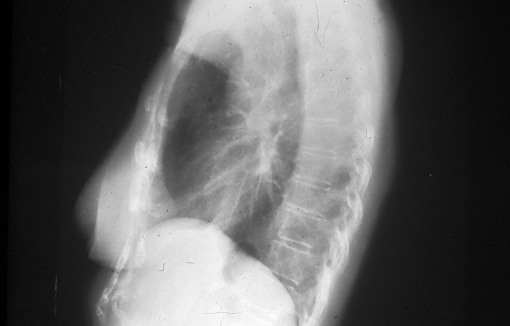

Fig. 14a and 14b: Posterior-anterior and lateral chest radiographs showing total collapse of left lung due to a central bronchogenic carcinoma, T3.